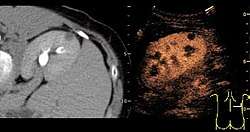

- Lesion Characterization: contrast-enhanced ultrasound plays a role in the differentiation between benign and malignant focal liver lesions. This differentiation relies on the observation[15] or processing[16][17] of the dynamic vascular pattern in a lesion with respect to its surrounding tissue parenchyma.